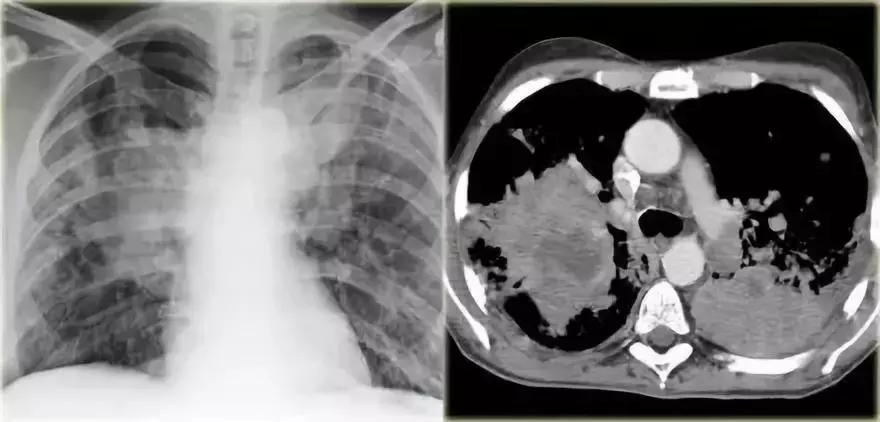

(2)病例

通过胸部X线,能发现什么,鉴别诊断是什么?

图14 多灶性实性病变

分析:

➢ 双肺多发阴影

➢ 右下肺边界模糊,阴影较大,可能存在空气-支气管征

➢ 可能会按照多灶性实变处理,同时需要考虑多发模糊团块的可能

➢ 呈现外周分布

➢ 患者无痰咳嗽数月,抗菌药物治疗无效。

➢ 在慢性实变范围内进行鉴别诊断

➢ 支气管肺泡癌和淋巴瘤癌的实验室检测指标正常

➢ 无嗜酸粒细胞增多症,排除嗜酸性粒细胞肺炎的可能

活检结果显示:机化性肺炎(OP)

图15 机化性肺炎(OP)